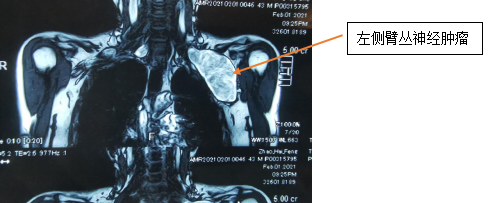

陈主任先安排患者进行相关检查,从体格检查、颈胸部增强CT、超声及磁共振结果来看,考虑患者左、右侧锁骨下肿物的性质为神经源性肿瘤——神经鞘瘤的可能性大。且目前左侧肿瘤已压迫胸腔,锁骨下良性肿瘤多数为神经源性肿瘤,特殊性在于肿瘤位于锁骨下,起源于臂丛神经,与锁骨下动静脉伴行。

2月4日,手外三团队进行术前讨论,一致认为患者右侧肿物较左侧小,患者右侧肿瘤未影响患肢活动,予左侧臂丛神经肿瘤切除,术后颈部空腔较大,出现皮下淤血,可导致呼吸困难、窒息可能,且肿瘤已压迫胸腔,稍有不慎胸膜破裂,有血气胸形成可能,手术风险较大。由于锁骨下方解剖困难,多数需要切断锁骨,切断锁骨还需内固定,二期再手术取出内固定,对患者造成较大损伤,因此陈主任手术团队制定出另一套损伤小、恢复快的方案——不切断锁骨,直接采取“锁骨上、下联合切口”,通过锁骨上、下切口于锁骨下做通道取出肿物手术方案。